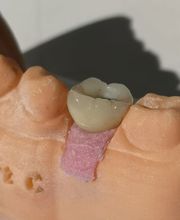

Seestrasse 160, 8806 BächZahnarzt · Zahnersatz · Kieferorthopädie · Implantologie

Seit 1995 dürfen wir Sie in Bäch an der Seestrasse willkommen heissen. Ihre orale und dentale Gesundheit ist und bleibt unser Hauptziel. Wir beraten Sie gerne auf dem Weg dorthin. Vereinbaren Sie noch heute einen Termin beim Zahnarzt oder der Dentalhygienikerin.